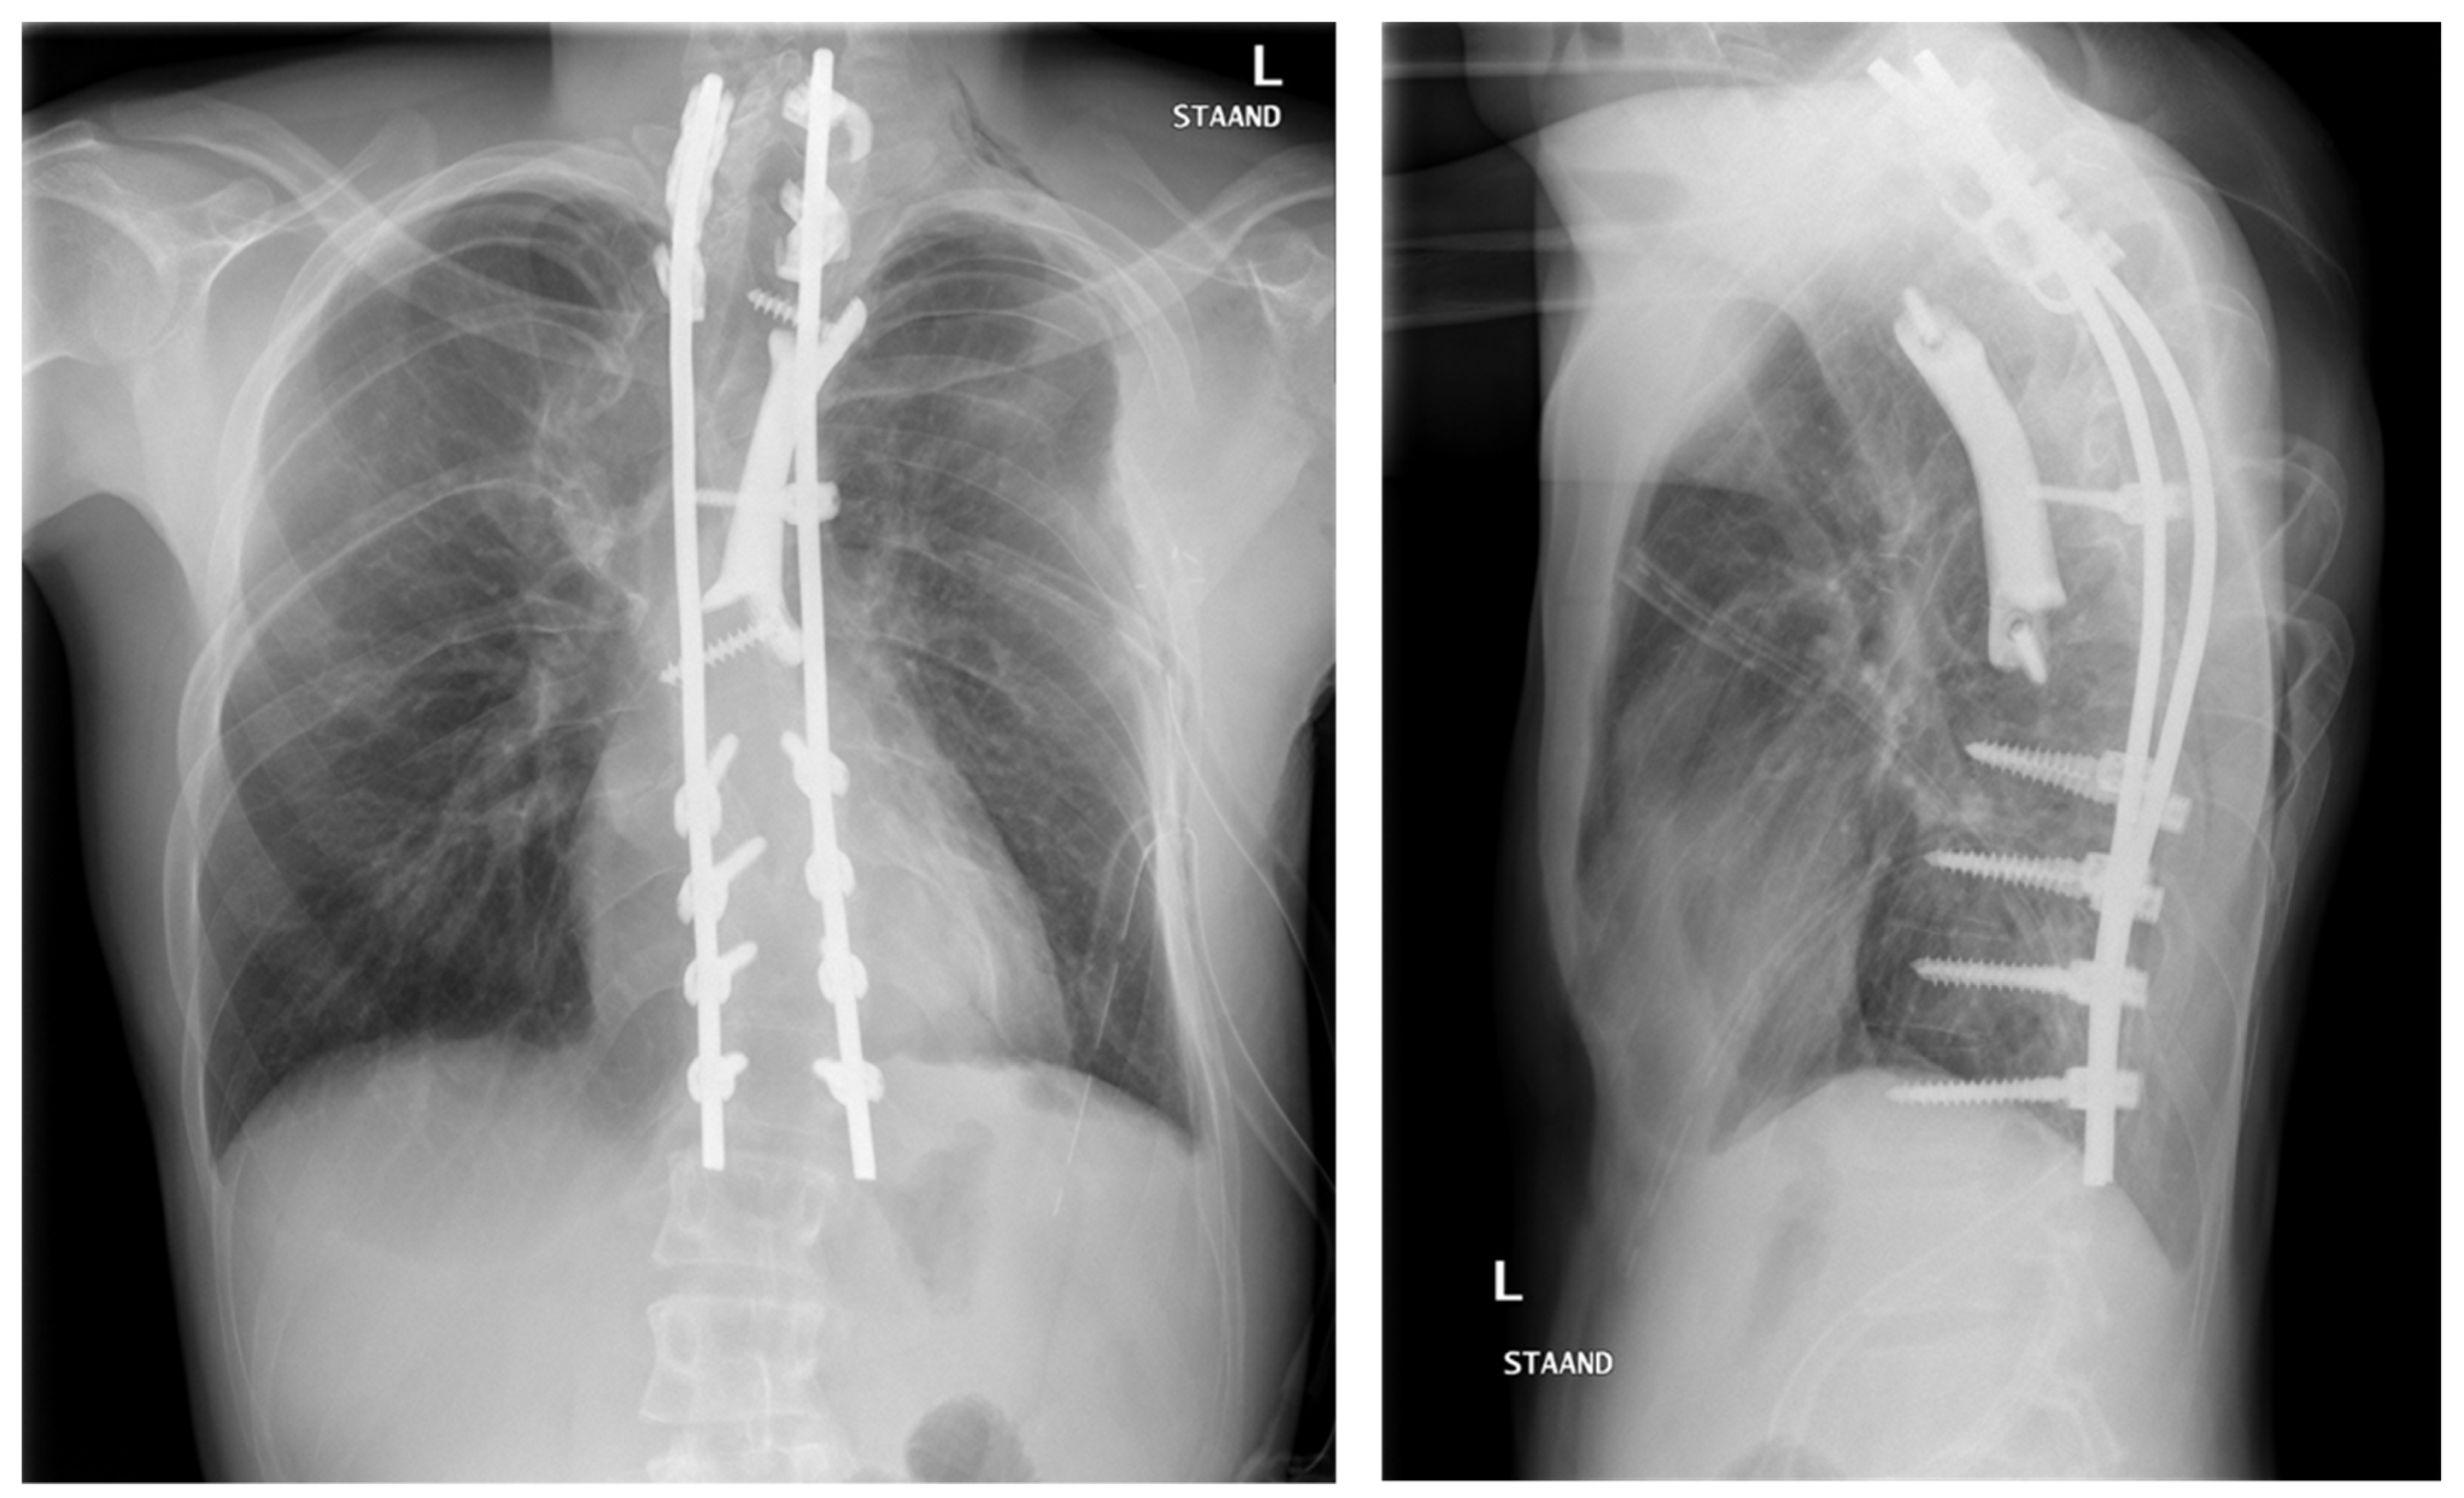

5. Pathway 2: Spinal Column Prosthesis

Background

6.3. Clinical Experience with Spinal Prosthesis